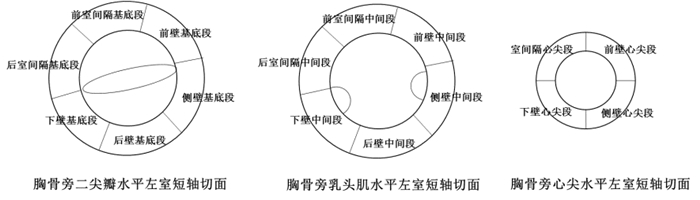

室壁运动同步失调、运动幅度减低(收缩期室壁增厚率<30%,心内膜运动<5 cm)、消失(心内膜运动<2 cm)、矛盾运动及正常节段室壁运动幅度增强(图 2)。常见于缺血性心肌病、心肌梗死或心肌炎。

| 图 2 左室16段划分 |